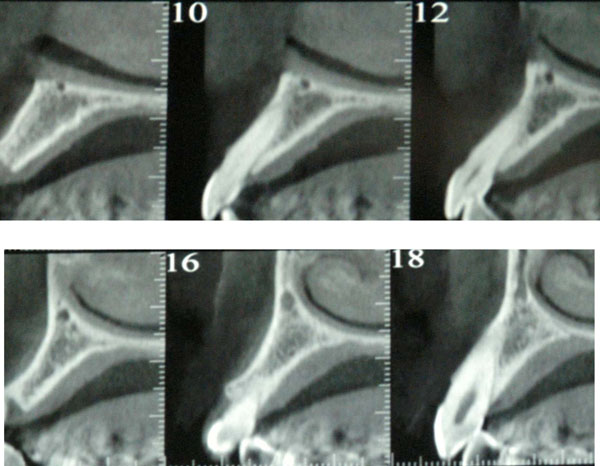

Fig. (2).

AAA identification through CT scan, cross sections.

The vascularity of the lateral wall of the maxillary sinus is not standardized and can vary greatly from individual to individual. The vascularisation of the maxillary sinus is in fact guaranteed from the internal maxillary artery, with its four branches: infraorbital artery, sphenoid-palatine artery, posterior superior alveolar artery and descending palatine artery. Posterior-superior alveolar artery has an average size of 2 mm and divides into two branches: the first gum branch runs superficially to the bone wall to supply the premolar and molar area and forms an anostomoses with extraosseous branch infraorbital artery at a distance of 23-26 mm from the alveolar ridge. The second branch, dental, forms an intraosseous anastomoses with infraorbital artery at the level of the anterolateral wall of the maxillary sinus at a distance of 18.9-19.6 mm from the alveolar ridge (Figs. 8-9). It is not always possible to identify this anostomoses, but the terminal branches of IOA and PSAA are always present in the anterolateral wall of the sinus [1] The positions of the extra-and intraosseous anastomoses therefore have a range of variability of 5 to 10 mm which can greatly affect the surgical procedure of the maxillary sinus. This variability depends in most cases by the degree of bone resoption that the alveolar ridge is subject to. In classes I, II and III [26] the literature reports an average distance of the vascular bundle from the most apical point of alveolar ridge of 19 mm [1, 10], and 16.4 mm [2], 16.9 mm [11]. In cases of severe atrophy (in classes IV, V and VI) the distance between the AAA and the crest is greatly reduced. This is shown by the data in the literature, 10.9 mm, 11.25 mm [11, 12].